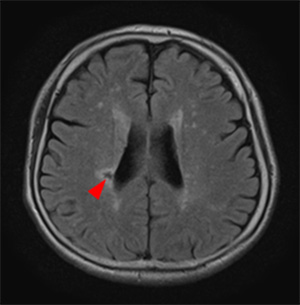

血管周囲腔の拡大

血管周囲腔の拡大は軽度であれば加齢変化の範囲内で病的意義はないとされています。ただし半卵円中心の血管周囲腔の拡大は高度になると認知症との関連が指摘されており、また大脳基底核の血管周囲腔拡大は高血圧症に関連すると考えられています。